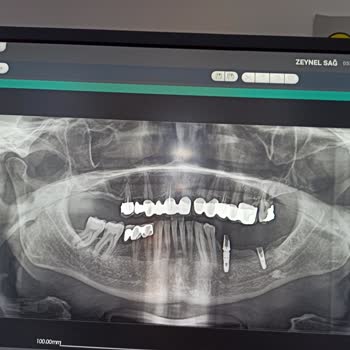

Yaklaşık 5 yıl önce Yeşiltepe Kliniği’nde Osstem implant yaptırdım ve bu süre boyunca implantımı sorunsuz olarak kullandım. Ancak 25.02.2025 tarihinde kemiğe saplı olan kısımda çatlama oldu, implant tamamen düştü ve ciddi mağduriyet yaşadım. Yaşanan bu ciddi arızaya rağmen klinik ve ilgili kişiler ...